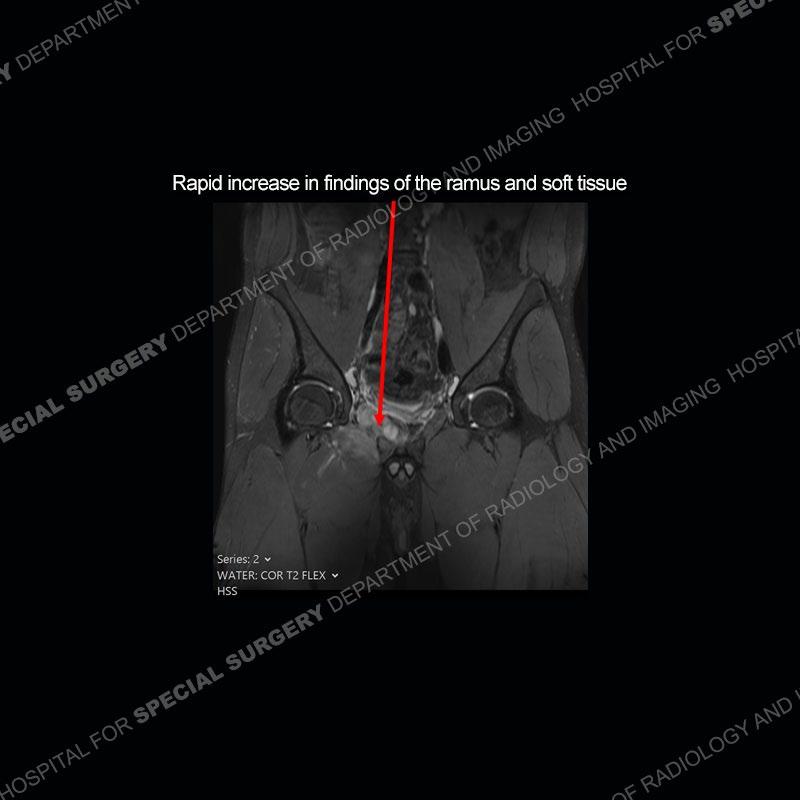

Subsequent MRI in a very short time interval shows markedly increased abnormality of the ramus and increased edema and “mass” of the soft tissue. Post contrast imaging shows multiple, rim enhancing collections of the soft tissue and similar albeit less conspicuous enhancing collection of the ramus.

The repeat MRI, with the marked degree of increased abnormality of the bone and soft tissue shifted the diagnosis to a high degree towards infection. Even the most aggressive of neoplasms would not have that the degree of change in a 3-day time span. The CT study was shown before the repeat MRI but actually occurred just after the repeat MRI. It helped confirm the destructive process of the ramus and particularly the abnormal architecture along the inferior margin. The patient went on to have a CT guided aspiration of one of the soft tissue collections with 4cc of purulent fluid obtained. A surgical irrigation and debridement of the bone and soft tissue was performed. A PICC line was placed and the patient is currently undergoing IV antibiotic treatment with a possible repeat irrigation and debridement.